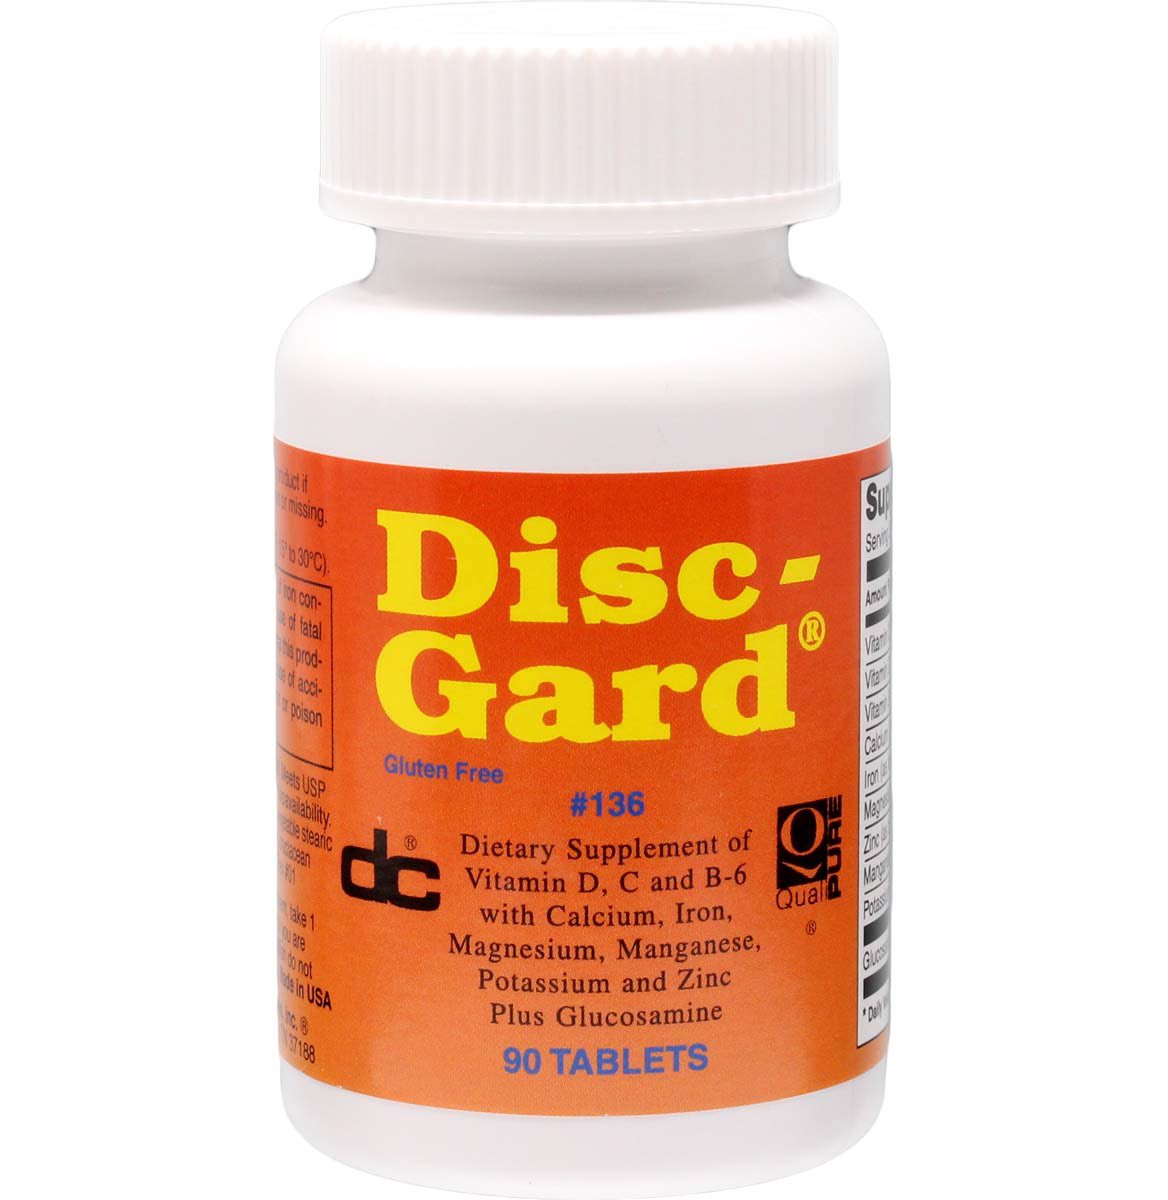

Check out this week’s video on DiscGard, a popular in house supplement used to strengthen soft tissue. LIKE AND SHARE facebook.com/share/v/SZDAFi… #discgard #discinjuries #spinaldisc #discbulge #discherniation #vitamins #minerals #naturalhealing

Do you have spinal disc damage? Learn how we can help improve the recovery process with DiscGard. #discgard #spinalhealth #spinaldisc #discherniation #discbulge #discherniationrecovery #nonsurgicalspinaldecompression #spinaldecompression facebook.com/share/1Za5eWHv…